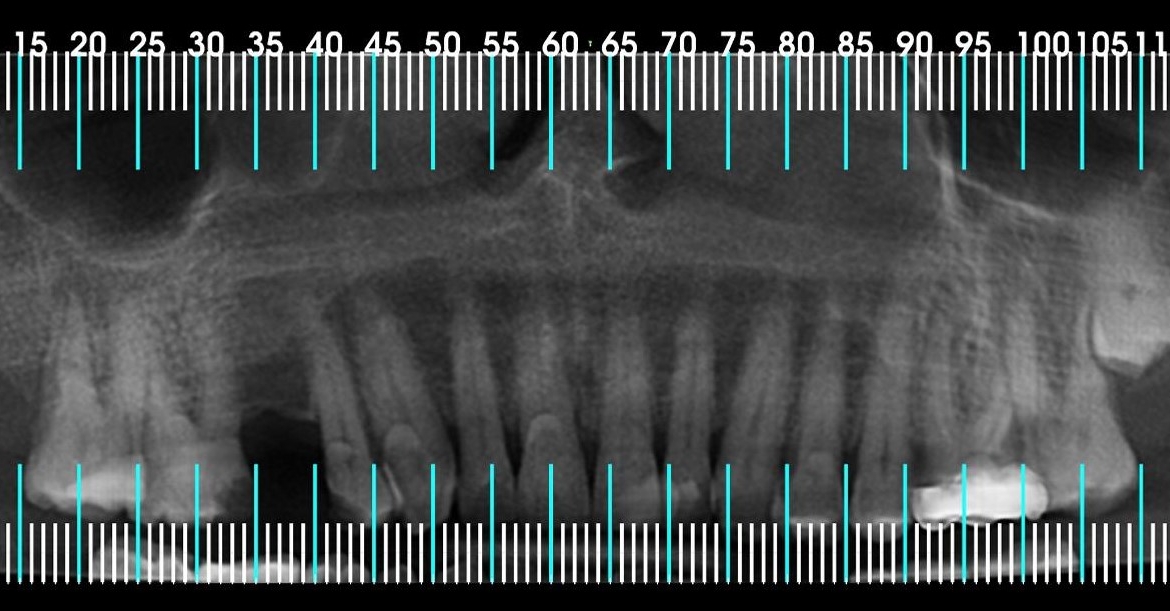

Avaliação de dentes inclusos e impactados

Com a utilização da Tomografia Computadorizada pode-se planejar, com grande sucesso, cirurgias de dentes inclusos, tanto em casos de rotina como mais complexos. As imagens em 3D facilitam o acesso ao local da cirurgia, aumentando a precisão e diminuindo os riscos durante o processo operatório. Garantindo mais segurança e conforto nos procedimentos cirúrgicos.